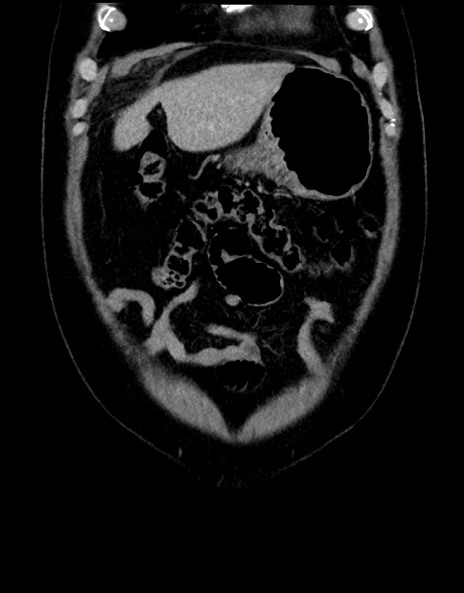

症例15(冠状断像)

【症例】70歳代男性

【主訴】腹痛

【現病歴】今朝から腹痛あり。全体的に痛い。特に左上の方。排ガスが今日はない。冷や汗が出る。

【既往歴】直腸癌術後

【身体所見】左側腹部〜上腹部に圧痛あり。腹膜刺激症状明らかなではない。軽度反跳痛。左下腹部に術後瘢痕あり。

【データ】WBC 7700、CRP 0.02